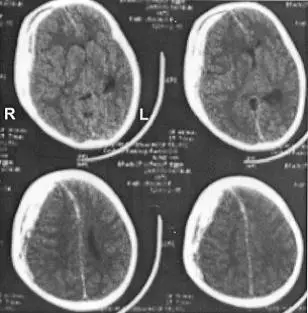

腦部電腦斷層掃描如附圖,顯示何處出血?

圖片為腦部軸向(axial)CT掃描,顯示4張不同層面的切面,影像左上角標示有「R」(右側)和「L」(左側)。

主要發現:

- 右側(R側):上層切面可見右側大腦半球表面存在一明顯高密度(hyperdense)雙凸形(biconvex/lenticular)病灶,緊貼顱骨內板,形狀如「凸透鏡」,邊界清晰。出血區域未跨越顱縫(suture line)。

- 左側(L側):相對正常,無明顯異常高密度區域。

- 腦部中線結構:可觀察到輕度中線偏移(midline shift),腦室受壓。

影像特徵判讀:

- 雙凸形(biconvex)高密度病灶 → 硬腦膜上腔出血(epidural hematoma, EDH)的典型 CT 特徵

- 位置在右側半球,位於硬腦膜與顱骨之間的硬腦膜外(上)腔

- 病灶不跨越顱縫,符合 EDH(硬腦膜與顱縫緊密黏附,限制出血範圍)

→ 結論:右側硬腦膜上腔(右側 epidural hematoma)出血,即選項 (C)